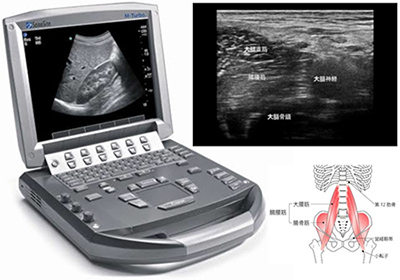

1.問診では、『超音波画像診断装置(エコー)』を用いるので、画像から硬く凝り固まったインナーマッスルの状態が一目瞭然。